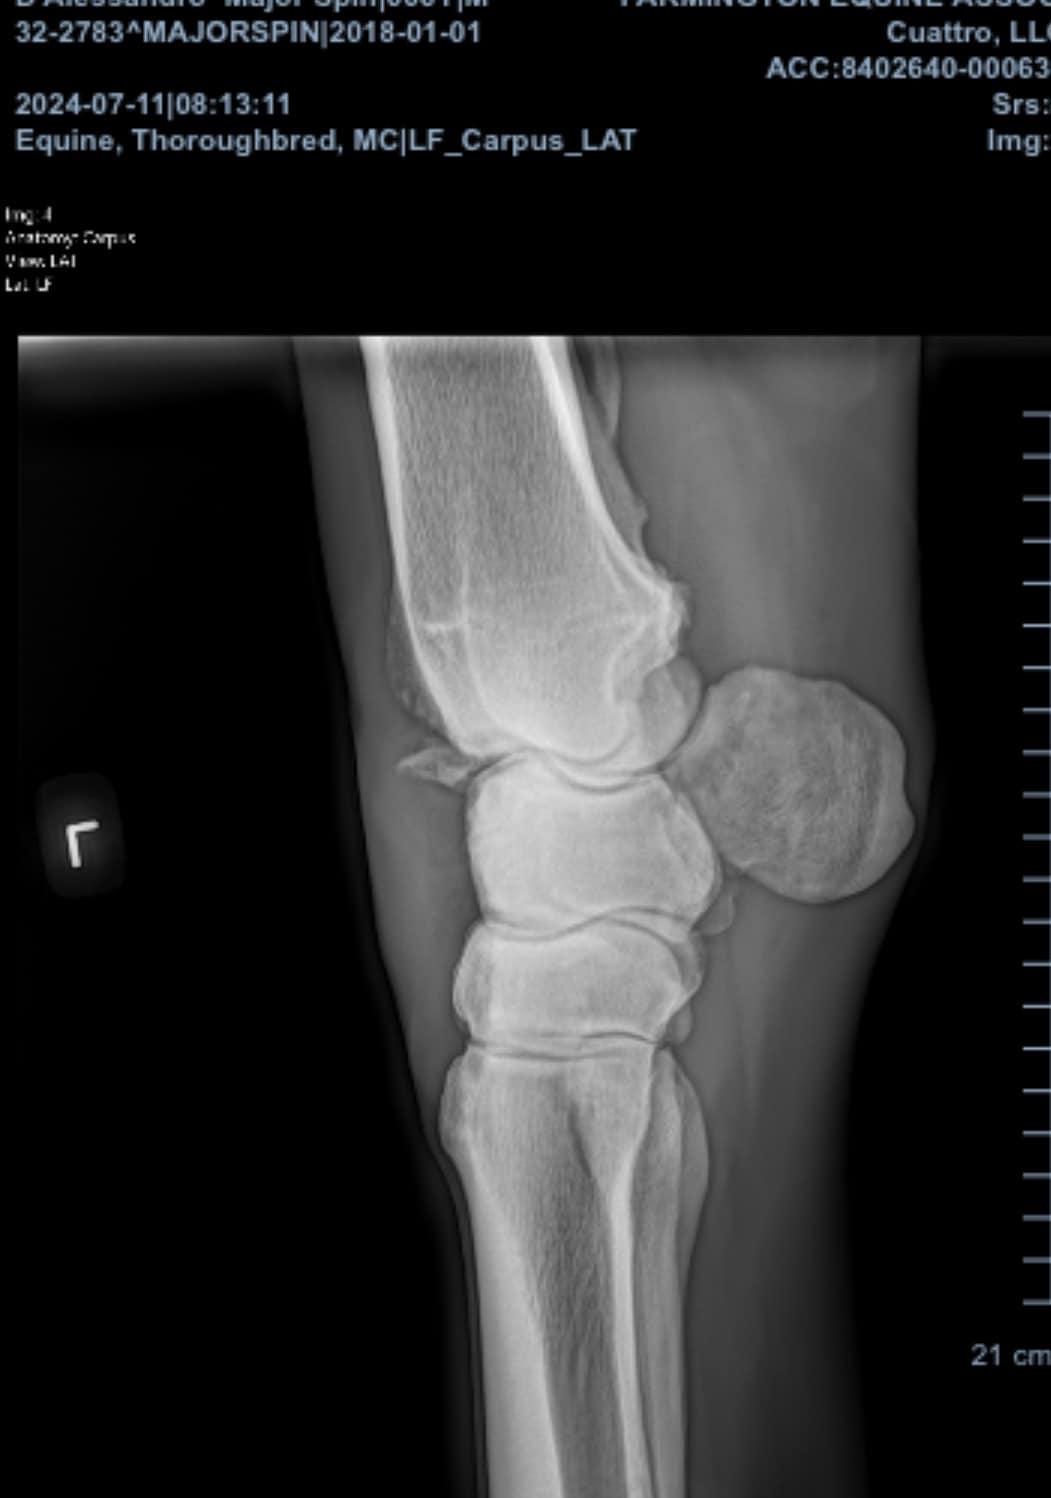

But Major Spin made it. When I first met him, he was still in the running line up at Finger Lakes Racing, despite being dead, dead lame on his left knee. It was so egregious that when the race trainer would not X-ray, the track vet donated their time and the films to us to help get him out of that situation. And so, because I’m a sucker, I did. I bought Spin (yep, you heard that right — that trainer wouldn’t let him go for free, lame as hell to a good home… what a great guy…) and decided that we could make a decision about his future after a few months of turnout. And with time and rest, he kept getting better. And then he simply was sound.

With the help of the Stall Thirteen non-profit Spin got a chance to rest his knee for six months, then get restarted for a second career. We pointed him at dressage (since I don’t want to risk the knee in a jumping discipline) and the big horse took to it like a fish to water. In the lead up to the Makeover, I managed to get Spin to a couple dressage shows in the region. These let him see an arena, run the tests, and try his hand at surviving chaotic warmup arenas before he got to Kentucky. Good kid.

At the Makeover, he sand danced his way into the top third in dressage, despite a knee that looks like it should never in a million years be sound. But perhaps most importantly, on day one in Kentucky, he passed his soundness exam — slab fracture, huge chip, arthritis and all. He actually is sound. It is wild, unlikely, and frankly damn wonderful.

Throughout the week at the Makeover, Spin was a giant gentleman. He schooled well daily with only one hitch: the barrel racers. Apparently Spin thinks neon fringe is worthy of terror. But with them out of sight, he laid down a quality Training Level 2 test and freestyle (which was mostly Training Level Test 3). The only hitch there came as I heard the bugle… then came the galloping herd of fox hunters and hounds racing across his line of sight during his attempted free walk in the T2 test. Too bad on timing, but what a good kid. He still pulled 8s on his trot work and went home with lovely comments and a ton more experience under his proverbial belt.

But with Spin — as with these horses who are there showing off not just what they have become post track, but what they have overcome from the track — the best part was that he arrived sound, he competed sound, and he shipped home sound. I’m thrilled with his brain and the quality of work he put forth, but I’m even prouder of the sheer fact that he was able to do any of it in the first place. Ride the horse, folks, not the X-ray.